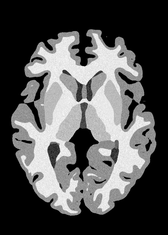

4.2 Registration to a 100 micron ex-vivo brain MRI volume

To showcase the efficacy of our method on real large scale images, we register a 250 in-vivo MRI image (Lüsebrink et al., 2017) to a 100 ex-vivo FLASH human brain volume (Edlow et al., 2019). This represents an inverse problem with more than 11.2B optimizable parameters (compared to 20M for clinical datasets), or 44.8GB of GPU memory. The entire problem does not fit on most GPUs, necessitating distributed multimodal registration. We optimize a composite transform - affine followed by a diffeomorphic mapping; details can be found in Section E.1. Multimodal deformable registration took 58 seconds on 8 NVIDIA A6000 GPUs, which is unprecedented at this resolution. Fig. 6 shows qualitative results, highlighting the ability to register highly detailed structures such as cerebellar white matter; these structures are not visible at macroscopic scales. The resultant advantages of performing registration at this scale can allow researchers to characterize the neuroanatomy at microscopic resolutions and allow morphometric analysis of cortical layers and subcortical nuclei among other structures.